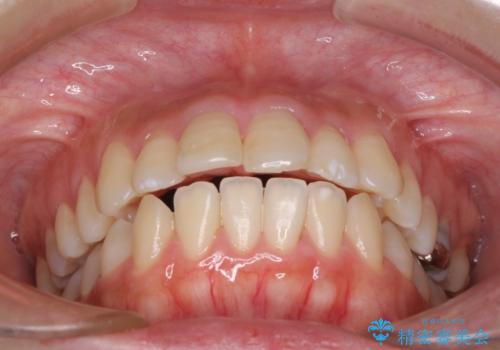

突出した口元が気になる ハーフリンガル装置による抜歯矯正

- 口元の突出感を気にして来院された患者様です。

通常では上下左右の第一小臼歯4本を抜歯しますが、下顎が左側にシフトしていたため、下顎左側のみ第二小臼歯を抜歯し、正中を合わせながら口元を下げる治療計画としました。

ハーフリンガルは、通常では表側のワイヤー矯正よりも治療期間がかかります。特に今回のように下顎左側をイレギュラーの第二小臼歯抜歯としたため、さらに時間がかかることが予想されました。

実際に治療をおこなってみると、2年を切る短期間で治療を終えることができました。